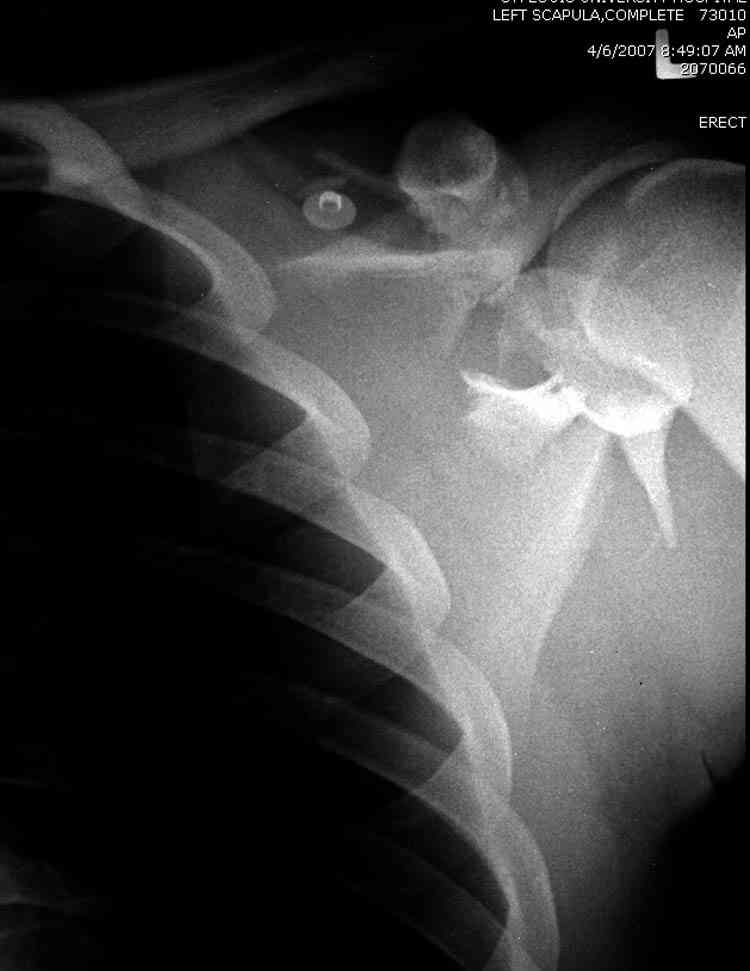

Для решения насчет оперативного вмещательства на лопатке сперва надо определиться с обьязательными ренгенологическими исследованиями, не менее трех стандартных проекций: прямая, аксиллярная и в позиции виде “Y”.

Прямую снимают под углом в 35 градусов от центра и вид “Y” в 90 градусов к нему. Несмотря на неудобства, больному необходимо сделать

аксиллярный снимок.

К-томографические и Трехмерные(3D)снимки крайне важны для определения внутрисуставных переломов и классификации.